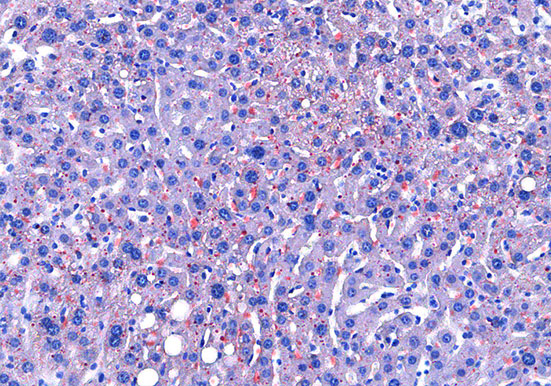

油红O染色

技术原理油红O对脂滴的染色机制一般认为是物理学上的溶液作用或吸附作用,借溶液作用使脂质染色,即油红O先溶于60%异丙醇中,然后切片浸入油红O染液中时,油红O在组织脂质的···